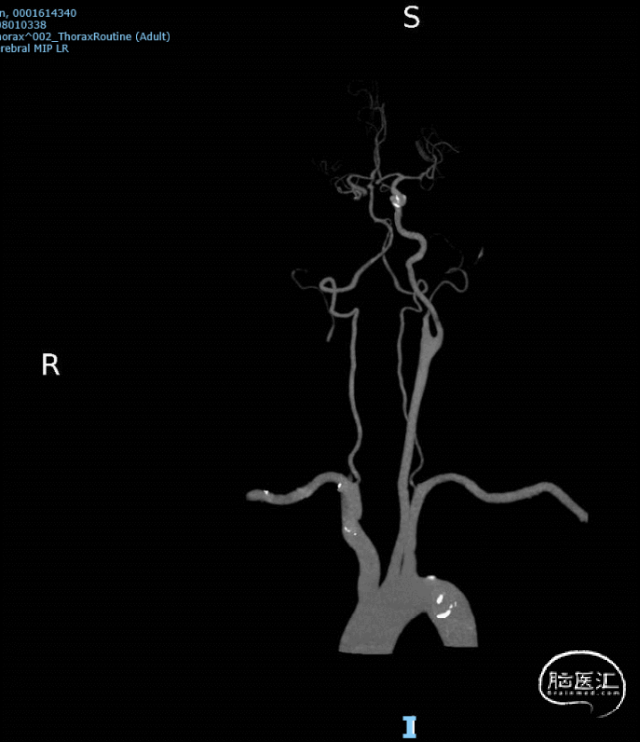

急查颅脑CT+脑动脉CTA:右侧颈总动脉、颈内动脉重度狭窄或闭塞,右侧大脑中动脉M1段重度狭窄或闭塞。结合入院心脏彩超提示存在心房血栓,考虑栓塞事件,患者家属同意后急诊手术。

术前DSA:右侧颈内动脉栓塞,可见“大栓子”。